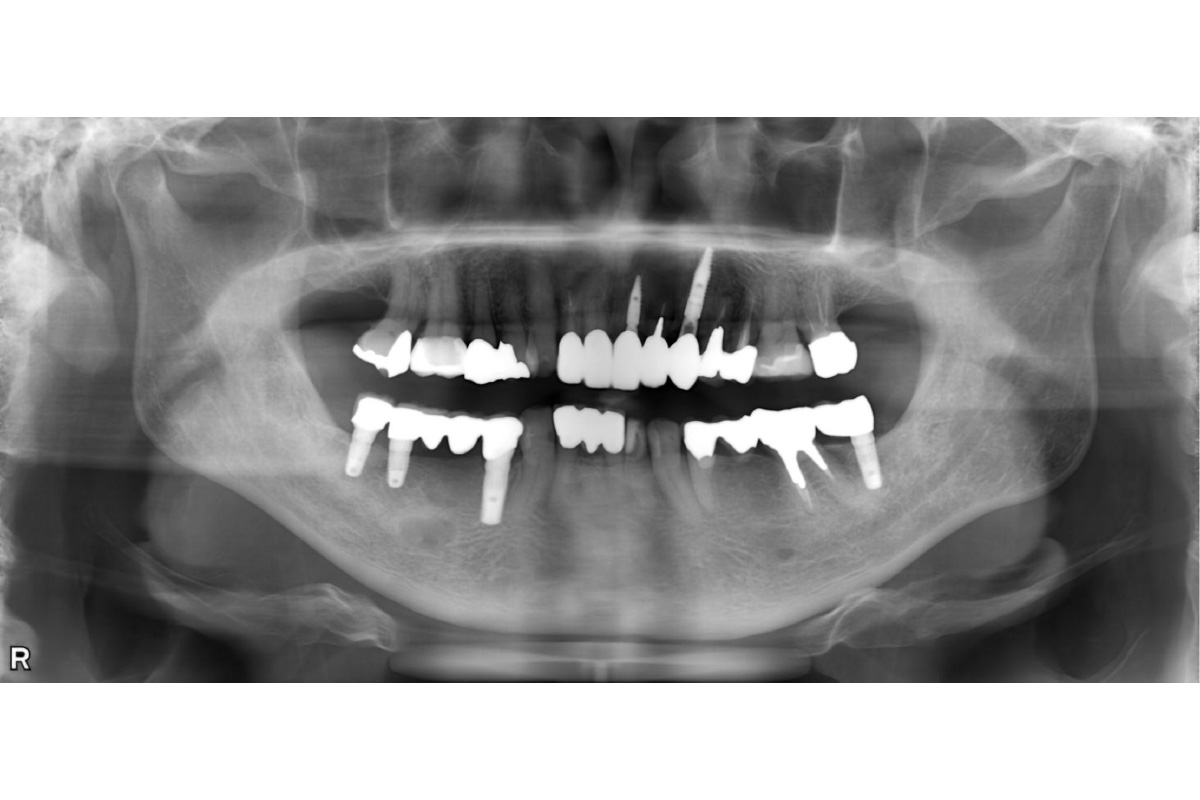

インプラント治療審美歯科 ジルコニアクラウン前歯をキレイにしたい骨造成 2026.03.12 前歯の抜歯が必要となった。隣の歯も含めてキレイに治したい。 治療前 治療後 治療前 インプラント 治療後 担当医 小林 健一 先生 主訴 前歯の抜歯が必要となった。 隣の歯も含めてキレイに治したい。 期間 6ヵ月 費用 1,179,200円(治療時) 治療内容 ジルコニアクラウン3本 インプラント治療2本 骨造成 治療に伴うリスク 外科処置を伴う 関連症例 インプラント治療 左下の奥歯を入れ歯以外で治したい 担当医 小林 健一 先生 主訴 左下の奥歯を入れ歯以外で治したい 期間 6ヵ月 費用 1,152,800円(治療時) 治療内容 抜歯・骨造成 インプラント治療 治療に伴うリスク 外科処置を伴う 2026-03-11 奥歯のインプラント骨造成 インプラント治療 下顎の入れ歯の安定が悪い。美味しい食事を取りたい。 担当医 小林 健一 先生 主訴 下顎の入れ歯の安定が悪い。美味しい食事を取りたい。 期間 5ヵ月 費用 2,457,400円(治療時) 治療内容 インプラント治療(フラップレス手術) 治療に伴うリスク 外科処置を伴う 2026-03-11 しっかり噛めるようになりたい入れ歯が合わない インプラント治療 左上の前歯が折れた。インプラントで治したい。 担当医 小林 健一 先生 主訴 左上の前歯が折れた。インプラントで治したい。 期間 4ヵ月 費用 628,650円(治療時) 治療内容 インプラント治療(抜歯即時埋入) 骨造成 結合組織移植術 治療に伴うリスク 外科処置を伴う 2026-03-23 前歯が折れた抜歯即時インプラント結合組織移植術骨造成 インプラント治療 前歯が折れた。抜歯はいいが、残りの歯を削らずにインプラントで治したい。 担当医 小林 健一 先生 主訴 前歯が折れた。抜歯はいいが、残りの歯を削らずにインプラントで治したい。 期間 5ヵ月 費用 686,400円(治療時) 治療内容 インプラント(抜歯即時埋入) 骨造成 カスタムアバットメント作成 治療に伴うリスク 外科処置を伴う 2026-03-11 歯が折れた骨造成 インプラント治療 上顎の歯をキレイに治したい。治療費を抑えたい。 担当医 小林 健一 先生 主訴 上顎の歯をキレイに治したい。治療費を抑えたい。 期間 費用 2,500,000円(治療時) 治療内容 仮歯 インプラント補綴(オールオン4) 静脈内鎮静法 治療に伴うリスク 外科処置を伴う 2026-03-11 オールオン4上顎の歯をキレイに治したい治療費を抑えたい インプラント治療 抜歯となった。インプラントで治したい。 担当医 小林 健一 先生 主訴 抜歯となった。インプラントで治したい。 期間 4ヵ月 費用 455,950円(治療時) 治療内容 インプラント治療(抜歯即時埋入) 骨造成 治療に伴うリスク 外科処置を伴う 2026-03-11 抜歯即時インプラント骨造成 インプラント治療 左下の歯を入れ歯以外で治したい。前歯のブリッジはそのままで治したい。 担当医 小林 健一 先生 主訴 左下の歯を入れ歯以外で治したい。前歯のブリッジはそのままで治したい。 期間 5ヵ月 費用 566,500円(治療時) 治療内容 骨造成 結合組織移植術 インプラント治療 治療に伴うリスク 外科処置を伴う 2026-03-11 結合組織移植術骨造成 インプラント治療審美歯科 前歯をインプラントで治したい。両隣の歯も揃えてキレイにしたい。 担当医 小林 健一 先生 主訴 前歯をインプラントで治したい。両隣の歯も揃えてキレイにしたい。 期間 4ヵ月 費用 899,800円(治療時) 治療内容 右上中切歯へのインプラント治療 (骨造成、結合組織移植) 両隣在歯のジルコニアクラウン 治療に伴うリスク 外科処置を伴う 2026-03-11 ジルコニアクラウン両隣の歯も揃えたい結合組織移植術骨造成